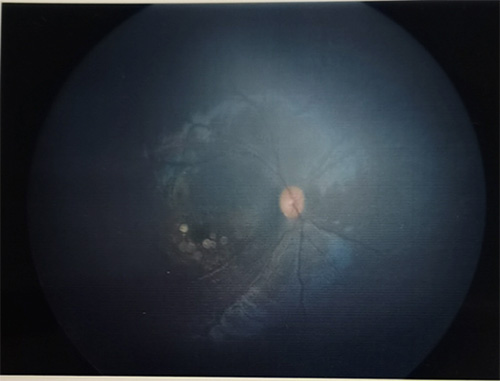

一天,一个6个月大的孩子在北京儿童医院检查眼底时发现竟然有“黄斑变性”!家长说:孩子6个月了还不追物,追光也不好。眼底黄斑区是一圈圈的圆片状色素异常。

黄斑区异常

甲基丙二酸血症(MMA)是一种由MMACHC基因突变引起的MCM或其辅酶钴胺素(维生素B2)的代谢障碍,从而引起甲基丙二酸、丙酸等有机酸在体内蓄积,造成患儿出现神经、认知、精神和血栓栓塞等异常发生。可在新生儿至成年期多个时期发病,在新生儿及婴幼儿期发病时多伴有严重的系统性疾病。症状可能包括嗜睡、发育迟缓、反复呕吐、酸中毒、脱水、呼吸窘迫,肌张力减弱、癫痫发作、智力落后。而在眼部主要表现为斜视、眼球震颤、不追光追物,检查眼底时发现黄斑区进行性色素萎缩病变、色素性视网膜病变、视网膜血管变化和视神经萎缩。

国外有文章报道显示,及时诊断及积极治疗可延缓眼底疾病的进展,但是存在个体差异。根据我们对确诊MMA的孩子进行眼科会诊发现,有些患儿可能在疾病的一定时期不合并眼底异常,但仍需定期监测眼底变化,有病例报道患儿诊断后随访过程中出现视力下降、眼底异常情况。